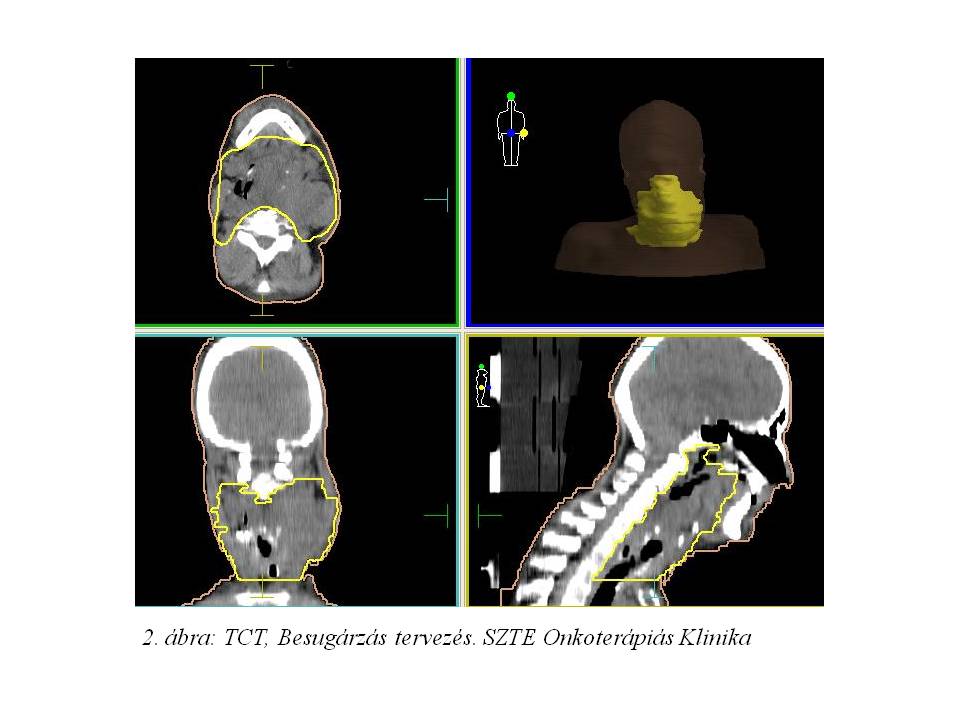

47 éves férfibeteg 2014 szeptemberében nagyfokú stridoros légzés miatt jelentkezett az SZTE Fül-Orr-Gégészeti Klinikán. Ekkor urgens tracheotomia történt. Korábban orvosnál nem járt, bár légzési és nyelési panaszai régóta fennálltak, továbbá kb. 20 kg-ot fogyott az elmúlt évben (több mint 25%-os súlyvesztés). Kivizsgálása során kétoldali fixált nyaki nyirokcsomó metasztázist adó, pajzsporcon áttörő, a gége lumenét szinte teljesen kitöltő, gége porcot destruáló tumor igazolódott, mely a nyaki érhüvelyt diszlokálta, infiltrálta (Stádium IVA, T4 N2c M0) (1. ábra: Nyaki lágyrész CT 2014.10.11.).

Multidiszciplináris team (fül-orr-gégész, onkológus, sugárterapeuta) döntése alapján indukciós TPF (Docetaxel, Cisplatin, 5-FU) kemoterápia nem jött szóba a beteg igen gyenge általános állapota miatt. Definitív kemo-radioterápiát kezdtünk (2. ábra: TCT, Besugárzás tervezés), azonban intermittálóan jelentkező, convulsiv, flexiós tónusos görcsökkel járó rosszullétek miatt SBO-ra került, kezelését nem tudtuk folytatni. Ezt követően neurológián obszerválták, epilepszia irányába további vizsgálatok történtek. EEG epilepsziát nem igazolt, a convulsiv rosszullétek hátterében hypoxiás epizódokat véleményeztek. A hypoxiát a nagy kiterjedésű nyaki nyirokcsomó konglomerátum általi carotis sinus baroreceptor kompresszió okozhatta.